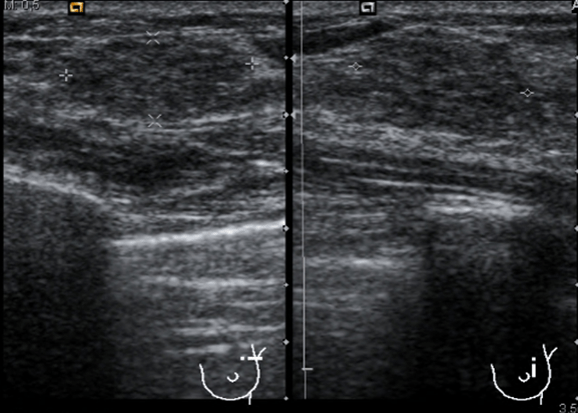

Las medidas tanto en transverso como en longitudinal, imagen 3 y 4 son importantísimas, hemos hablado anteriormente que la medida tiene relación directa con el diagnóstico diferencial de estas patología tumorales, y como no, la vascularización, que la ves en la imagen número 5 y que está aumentada, usaremos doppler color, imagen 5, y doppler power, imagen 6.

La ecografía muestra un tiroides multinodular, porque tiene otros tipos de imágenes nodulares al margen de la lesión estudiada. Adyacente al LTD y en contacto con la carótida común se observa una lesión nodular, sólida, no es anecoica ni tiene este componente, por tanto se considera sólida, hipoecogénica, que mide 10 x 9 mm y que por su localización y morfología es compatible con un adenoma de paratiroides inferior derecha, anatómicamente suelen ser 4, dos por lóbulo, una en polo superior y otra en el inferior…Hasta el próximo Post.